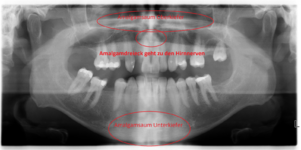

Ich habe auf Toxcenter endlich (aus dummen Zufall) die Bilder gefunden wo man Kieferaufnahmen erkennt, bewertet wurden, sowie auch Hirnaufnahmen.

https://web.archive.org/web/2014081...er.org/atlas-der-giftherde/index-bilder.php?0

Jetzt kann ich endlich versuchen mein OPG zu deuten. Ferner habe ich meinen Zahnarzt darum gebeten mir eine Überweisung zur Radiologie zu geben damit ich ein Vergleich des Kiefers vor und nach der Sanierung habe. Und auch um die aktuelle Belastung mit den Bildern und Dokumentationen von Toxcenter bewerten zu können. Oder es zumindest zu versuchen. Obs stimmt oder nicht wäre sowieso egal da sich an meiner Therapie nichts ändern wird. Das einzige wäre das sich Amalgamsplitter im Kiefer befinden. Die müssten dann operativ entfernt werden. In meinen Fall wären das 2 Zähne.